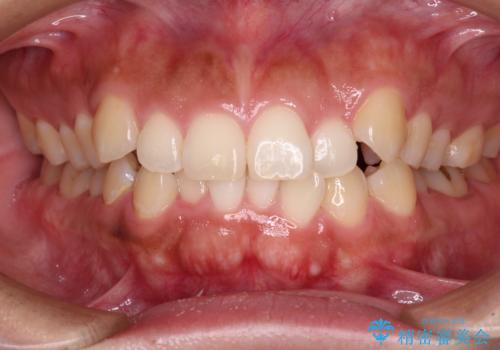

【モニター】カリエール・ディスタライザーを併用した八重歯のインビザライン矯正

- 前歯の叢生と八重歯を気にして来院された患者様です。

目立たない装置を希望とのことで、インビザラインにて矯正治療を行うこととしました。

インビザライン単体で改善することも可能ですが、八重歯とその後方にある歯列を確実移動させないと、上下正中がずれてしまう可能性があります。

インビザライン単体での治療ではなく、カリエール・ディスタライザーという補助装置を併用して、より確実性を上げることとしました。

補助装置で八重歯を解消しながら、並行してインビザラインで歯列を整えることとしました。

カリエールディスタライザーを併用したことで、すっきりとした口元になり、上下の正中を合わせることができました。